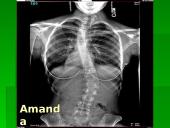

Skoliozė (S) formos

• Skolioze yra vadinamas pastovus šoninis stuburo iškrypimas, kai jis nukrypsta nuo vidurinės linijos. Skoliozės būna paprastos ir sudėtingos. Esant paprastai skoliozei, stuburas būna išlinkęs tik į dešinę arba į kairę. Sudėtingai skoliozei būdinga tai, kad vienoje stuburo dalyje būna pagrindinis iškrypimas, o kitose jo dalyse – kompensaciniai iškrypimai. Jei paprastas iškrypimas paliečia visą stuburą, tai jis vadinamas totaline, arba visiška skolioze. Iškrypus tik vienai stuburo daliai, skoliozė vadinama daline.